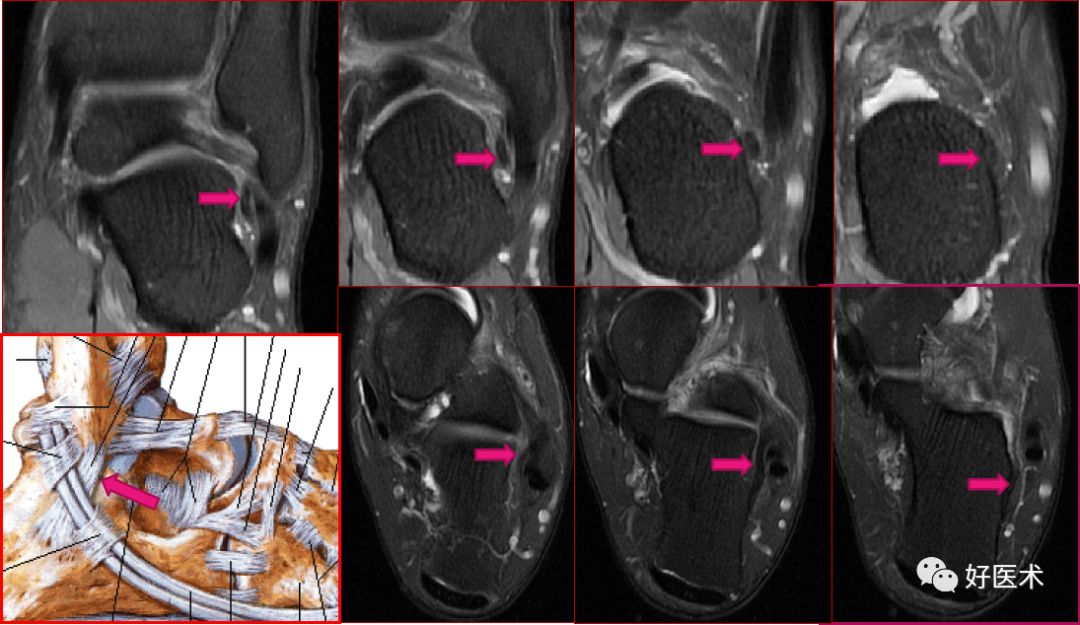

三角韧带

踝关节内侧韧带又称三角韧带,为强劲的三角形纤维束。上方附着于内踝尖及其前后缘;浅层纤维为胫舟部,前行附着于舟骨粗隆,部分与跟舟足底韧带的内侧面融合;中间部为胫跟部,下方附着于载距突;后部为胫距后部,纤维附着于至距骨内侧面和内侧结节。

三角韧带撕裂